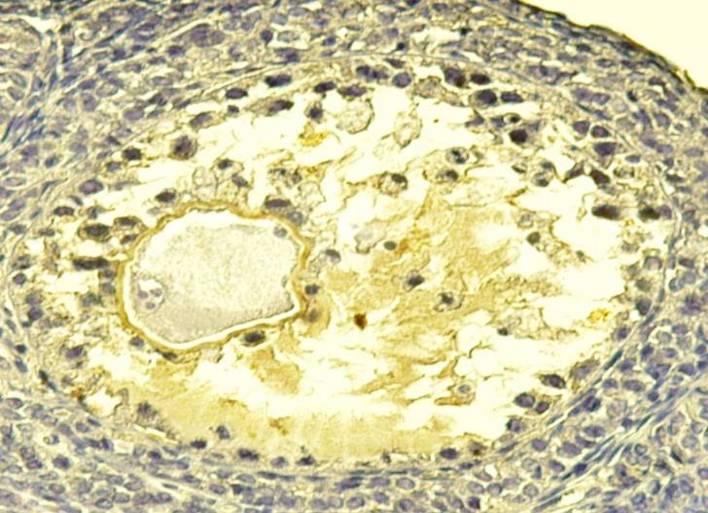

1. After three days of Adriamycin drug injection (A-I), it has been noted that the Graafian follicles were the most affected ovarian follicles. The toxicity of the drug caused the disappearance of the most of the natural Graafian follicles from the ovary. Furthermore, most of the follicles that have been seen in the ovary during this period are decomposed follicles with abnormal structures. In addition, a complete destruction of the Cumulus oophorous has been observed, with the spread of the Granulosa cells in the antrum. This is due to the loss of contact within the Granulosa cells, and the rush of its nuclei toward the antrum and the Zona pellucid. Consequently, this causes the destruction of the chromatin in some cells and its accumulation on the basement membrane of other cells, and thinning of the thickness of Theca folliculi. In addition, we noticed the presence of spaces in theca folliculi and migration of the Granulosa cells from the basement membrane, and partly the breadth of the Zonapellucidabecause of the loss of desmosomes between the oocyte and the cells. Regarding the Oocyte, the position of the nucleus is laterally with partial Granulosa decomposition of the nucleus membrane. In addition to the decomposition of the nucleus in some Graafian follicles (fig. 3), a clear reduction in the divisive ability of the Granulosa cells is seen compared to the normal control (fig. 4).

Fig. 3: Transverse section in Degradable Graafian follicles in the ovary of females injected with Adriamycin drug without protective dose (the first time (AI)-(H & Ix400) Fig. 4: Transverse section in Degradable Graafian follicles in the ovary of females injected with Adriamycin drug without protective dose (the first time (AI)-(Ki67x400)